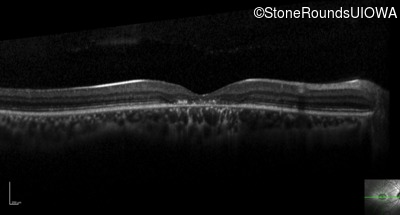

Optical Coherence Tomography - Left - 20/25 +2

Exemplar / OCT Stack

OCT Stack